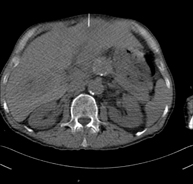

Prova diagnòstica que consisteix en obtenir imatges bi i tridimensionals de l'abdomen d'alta definició anatòmica (estructures òssies, estructures vasculars, fetge, pàncrees, vesícula biliar, ronyons, glàndules suprarenals, melsa, intestí prim i gros, bufeta, úter i ovaris, pròstata i vesícules seminals, urèters, etc.) mitjançant l'ús d'un equip de TC (Tomografia Computeritzada). La majoria d'estudis requereixen l'ús de contrast iodat. - TC Fetge

Prova diagnòstica que consisteix en obtenir imatges bi i tridimensionals del ronyó i del sistema urinari d'alta definició anatòmica mitjançant l'ús d'un equip de TC (Tomografia Computeritzada). Està especialment indicat en aquells pacients en els quals se sospita que hi ha pedres al ronyó, infeccions urinàries de repetició. L'estudi es realitza sense utilitzar contrast iodat (només es casos determinats serà necessari completar l'estudi amb contrast iodat). - TC Pàncrees

Prova diagnòstica que consisteix en obtenir imatges bi i tridimensionals del pàncrees d'alta definició anatòmica mitjançant l'ús d'un equip de TC (Tomografia Computeritzada). Es realitza l'estudi abans i després de l'ús de contrast iodat en diferents "fases pancreàtiques" per poder valorar totes les estructures: parènquima pancreàtic, conducte pancreàtic o de Wirsung, unió bilio-pancreàtica, colèdoc, artèries pancreàtiques, artèria i vena esplèniques, duodè. Està especialment indicant quan hi ha sospita de lesió pancreàtica, en pacients amb pancreatitis aguda o crònica, etc. - Angio-TC Aorta abdominal